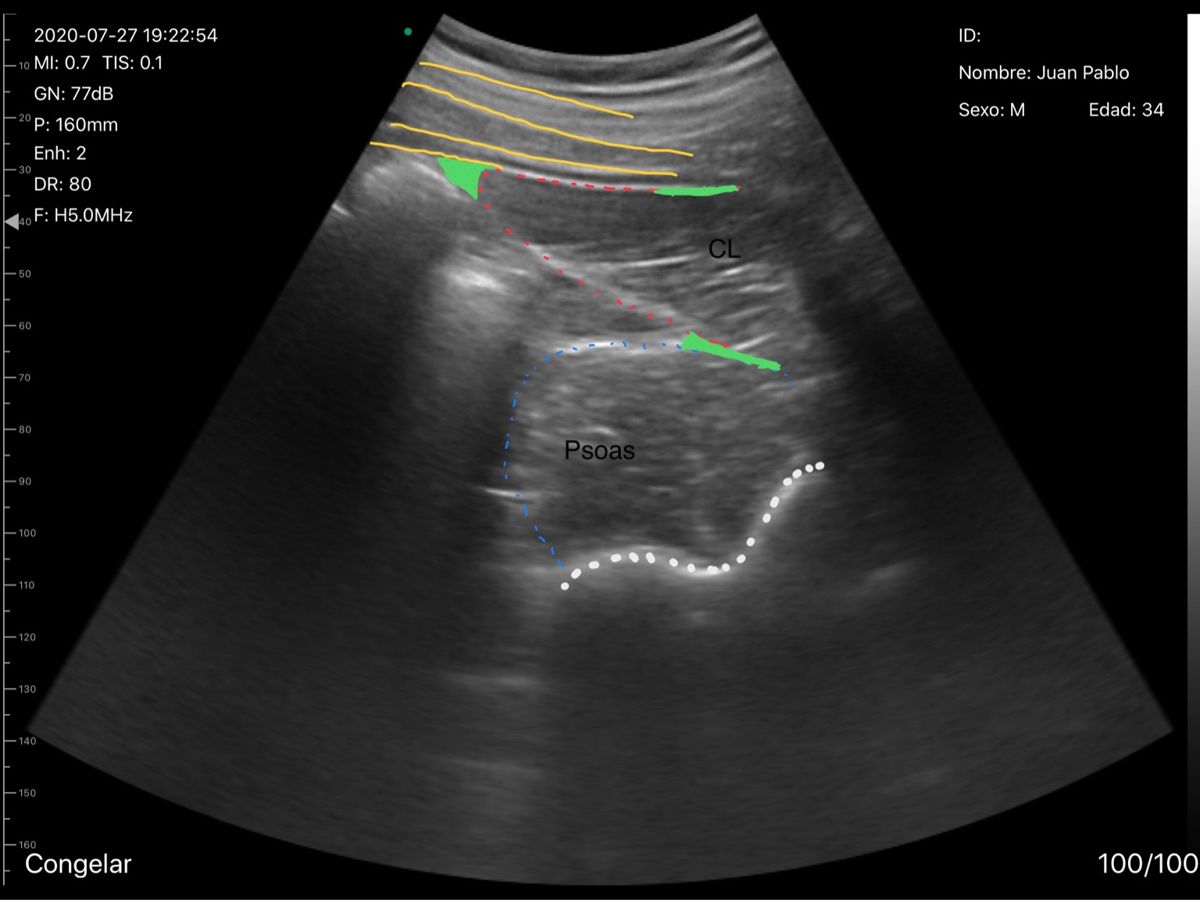

Ultrasonido región lumbar

Ultrasonido: permite ver tejidos blandos (músculos, vasos, trayecto del nervio) y dirigir la medicación sin radiación.